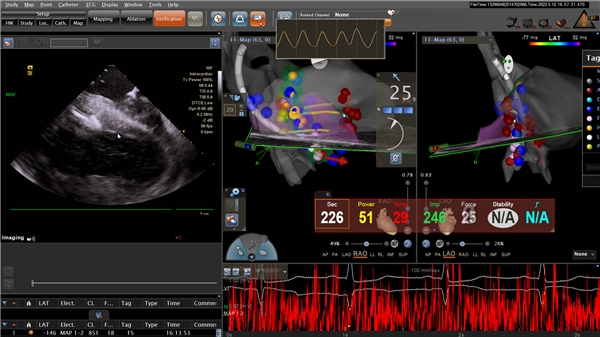

完善相关的术前检查后,王洪涛副主任医师带领蒋伟,孙阳医师、徐凯护师、徐一涛护师等组成的电生理团队为该患者行ICE(心腔内超声)指导下肥厚型心肌病室间隔射频消融术。首先经ICE构建左室及左室流出道解剖模型,并构建室间隔与二尖瓣叶前向运动接触区域(SAM征),拟为消融靶点。随后经股动脉鞘管送猪尾导管分别置于主动脉瓣上、瓣下,测术前主动脉瓣内压力68mmHg, 左室内压力95mmHg,压力差27mmHg。撤出猪尾导管,经股动脉鞘管送ST消融大头至左室间隔面,标测His及束支电位后,定位大头至室间隔最厚部位,功率35-55W放电消融,可见局部组织明确水肿,瘢痕挛缩。消融结束,再次经猪尾导管测量术后主动脉瓣内压力131mmHg,左室内压137mmHg,压力差6mmHg。术后裴女士未再发作心绞痛症状,胸闷、气短明显减轻。术后复查心脏彩超示左室流出道梗阻明显改善,康复出院。

ICE指导下室间隔射频消融术